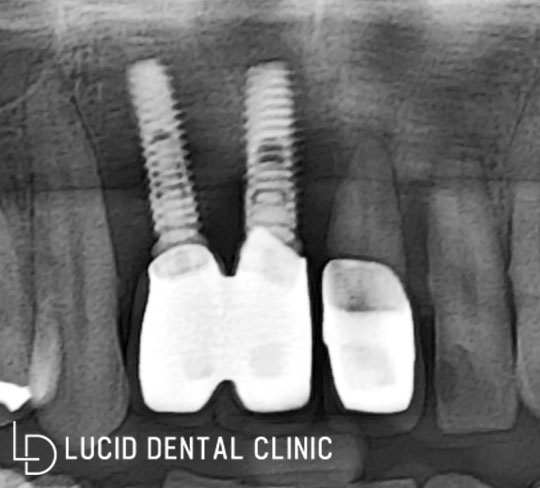

- 첫 번째 위쪽 앞니 (전치)

전치에 보철이 되어 있는데요.

뼛속에 박혀있던 픽스처가 골 소실과 감염으로 인해

뼈가 단단히 잡아주지 못해, 흔들리고 있었습니다.

- 두 번째 위에서 좌측 (소구치)

환자께서 통증이 있다고

말씀하기도 했고 뿌리도 내려와

동요(흔들림)가 나타나고 있었는데요.